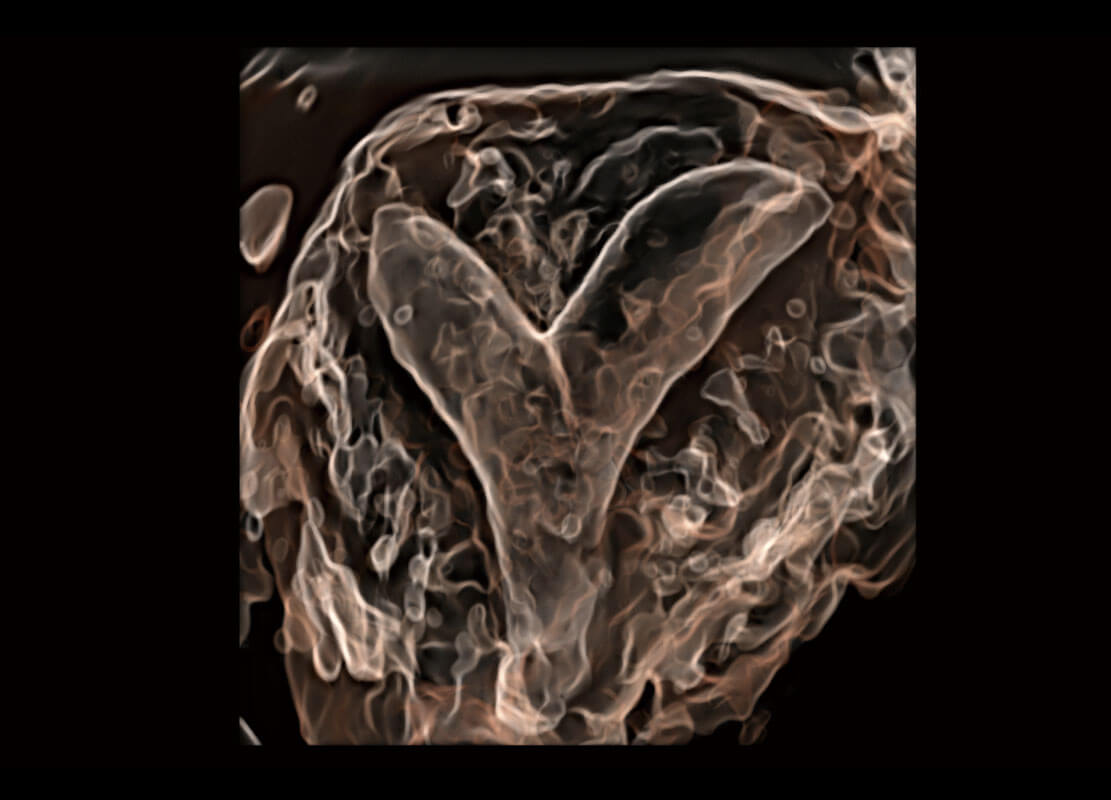

胎心筛查

P60搭载一系列胎儿心脏成像技术,实现精细的胎儿心脏评估。

• 胎心容积成像